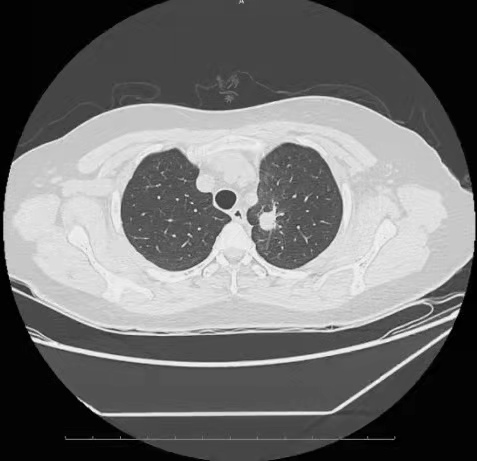

发病过程:2015年4月出现反复干咳少痰,无咳血,当地治疗诊治后未好转,2015年6月出现声音嘶哑,2015年7月6日当地行胸部CT:左肺上叶病灶,肺癌并阻塞性炎症可能,纵隔淋巴结肿大。2015年7月16日外院行胸腹CT:左肺上叶尖后段见一团块状肿物,大小约40mm×25mm,边缘毛糙,可见分叶和短毛刺,密度不均匀,内见小空腔影,增强呈不均匀强化,病灶下极紧贴纵隔胸膜生长,与左肺动脉分界不清。左肺下叶见多发结节,边界尚清,短径约3-5mm。颅脑MR未见明确占位性病变。支纤镜检查:声带麻痹,所见气管、各级支气管未见异常,病理不详。2015年7月20日我院就诊,患者2015年7月24日我院行肺穿刺病理:左上肺中分化腺癌(病理号151380)。于2015年7月30日、8月25日予2程TP方案化疗,疗效评价SD。结合2015年7月外院基因检测:19外显子突变,2015年9月开始服用埃克替尼。

▲2015年11月我院CT 左上肺病灶,16mm×15mm

▲2017年7月我院CT 左上肺病灶,26mm×16mm